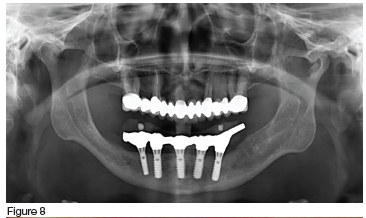

In the maxilla, the porcelain prosthesis remained intact with no fractures for 13 years (figures 8 & 9), however there was a single event of cement failure (figure 10) at year 12 in 2022. This event was easily managed through sandblasting the intaglio surface of the FPD and re-cementing it. The mandibular acrylic prosthesis also remained intact and functional for over 13 years, but did exhibit ±2.5 mm occlusal wear during this time. Additionally at year seven (2019) and year ten (2022) it had two separate events requiring replacement of the screw access hole closure material which had been lost (figures 9 & 11). No implant or framework complications were observed, nor was there any noticeable bone loss in either the maxilla or mandible (figure 8). The patient reported high satisfaction with both her aesthetics and chewing efficiency.